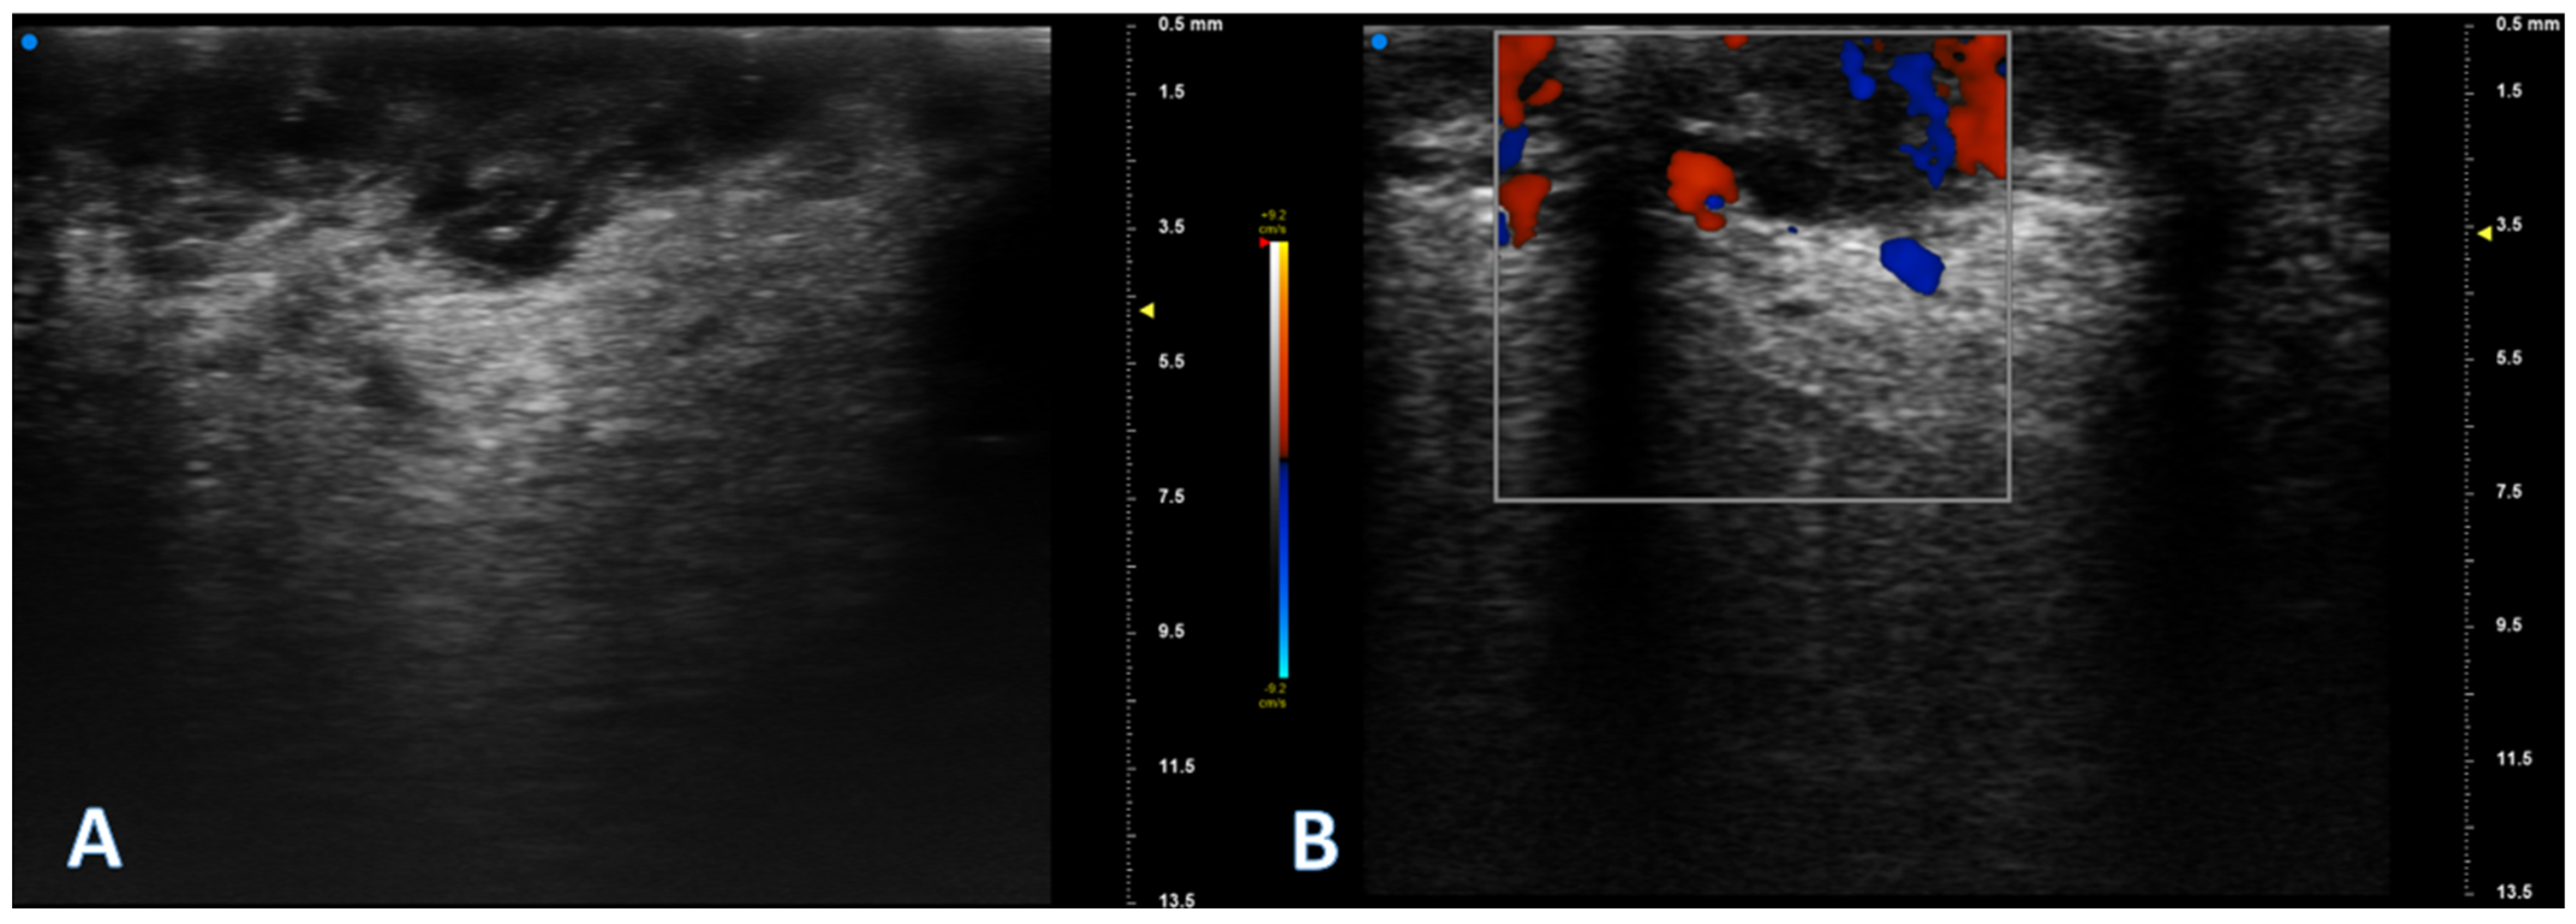

2.2. UHFUS Scan Protocol